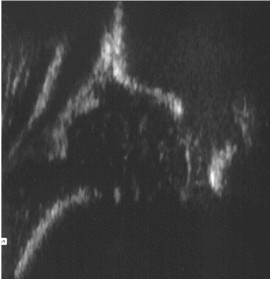

Przedstawiony ultrasonogram stawu biodrowego noworodka przedstawia następujący typ rozwojowy wg klasyfikacji Grafa: